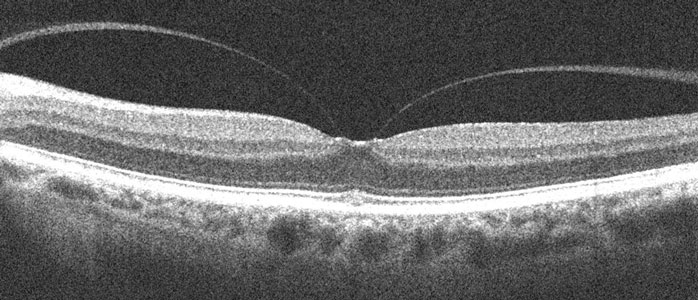

Throughout life the vitreous (the gel-like substance inside the eye) normally liquefies and gradually separates from the retinal surface. Although this usually results in a complete separation of the vitreous (posterior vitreous detachment), it can sometimes remain stuck to the central macula, the specialized area of the retina that gives us our straight-ahead reading and driving vision. Vitreomacular traction occurs when the adherent vitreous tugs and distorts the macula.

Treatment is often not necessary since many patients remain asymptomatic. Even with significant symptoms observation is often initially recommended since the traction can spontaneously release in up to 50% of cases. Treatment should be considered for those whose distortion, vision loss, and decreased depth perception make their daily activities such as reading and driving difficult.

Vitrectomy surgery is done in an operating room under local anesthesia. This advanced microsurgical technique restores vision by peeling the adherent vitreous from the macular surface, allowing the underlying macula to smooth out and function more normally. Patients go home immediately following surgery. There is usually minimal to no pain, except for minor irritation. Patients usually notice improved vision with decreased distortion within several weeks to months following vitrectomy although it may take much longer for maximal vision to return. The major surgical side-effect is a cataract, with many patients requiring cataract surgery within a year or two of vitrectomy. There is also a very small chance for secondary retinal detachment or infection.